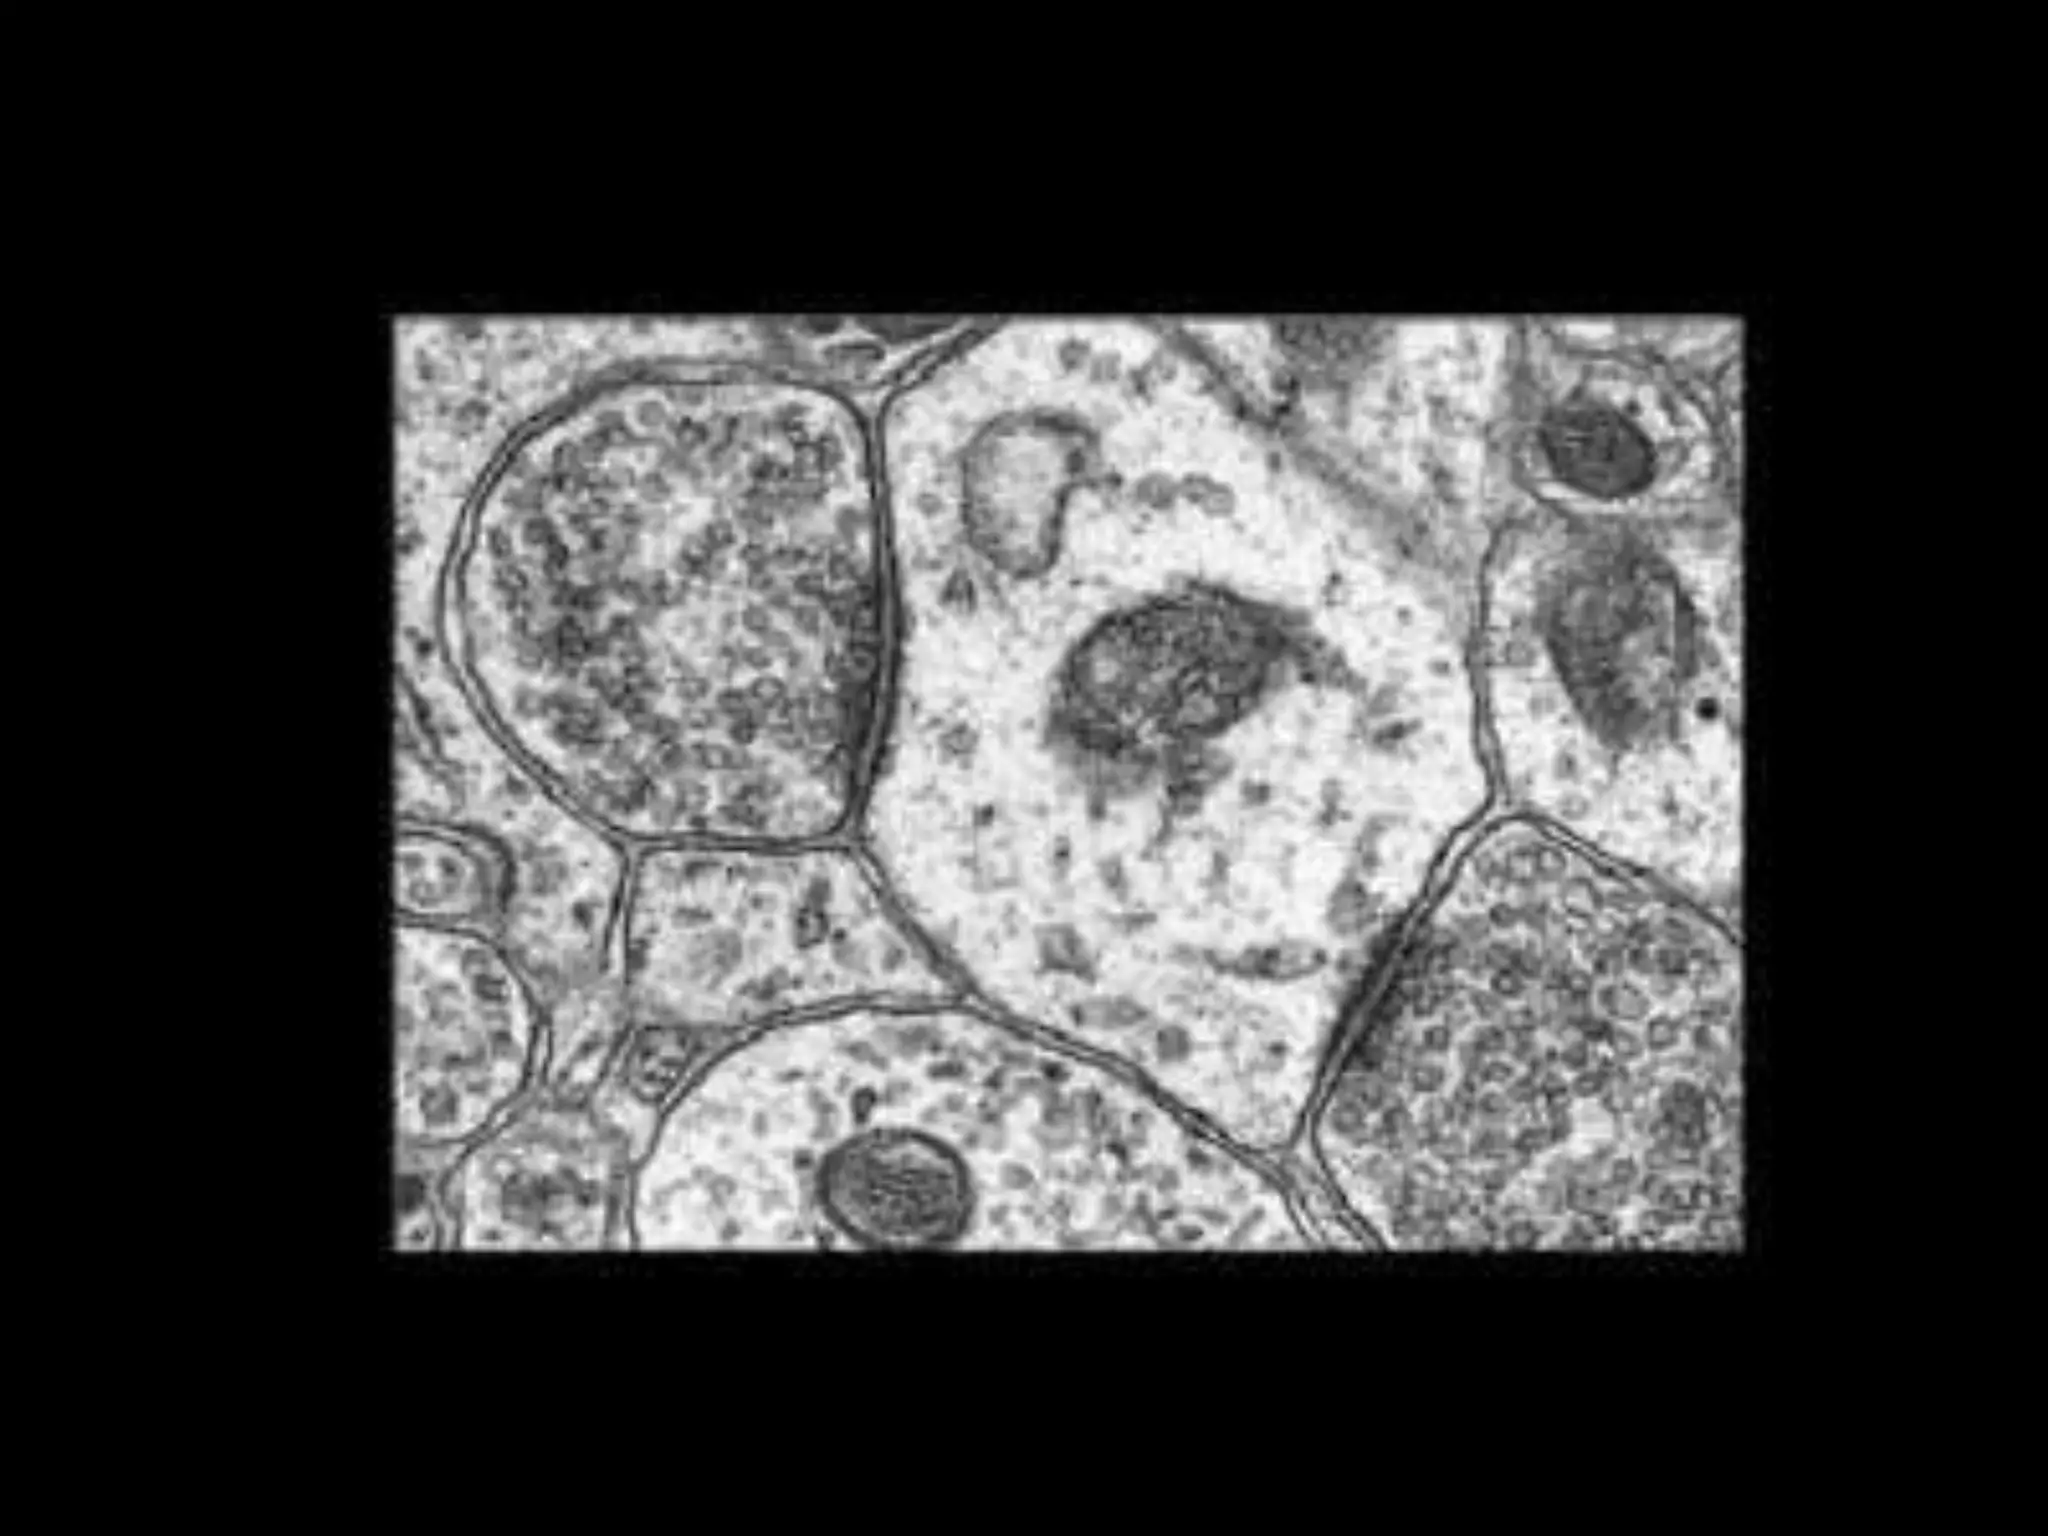

Neurotransmitters are packaged into synapticvesicles -

presynaptic side of a synapse.

Illustration of the major elements in chemical synaptic transmission.

Storage: They are packaged inside synaptic vesicles.

Release: They are released from presynaptic terminal by

exocytosis when calcium enters axon terminal

during an action potential